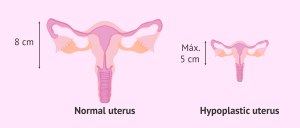

1- Nyababyeyi idateye neza (Uterine malformation): Iyo nyababyeyi ifite imiterere idasanzwe, (nko kuba igabanyijemo ibice bibiri, cyangwa ikaba nto cyane) , umwana ashobora kubura urwinyagamburiro, ntakure neza, bikagora kubyara.

Icyitonderwa ku miterere y’umugore mugufi cyangwa ufite bassin nto

Imiterere y’umugore ishobora kugira ingaruka ku buryo kubyara bigenda.

– Umugore mugufi cyane: akenshi aba afite bassin (pelvis) nto cyangwa ifunganye.

– Iyo bassin ari nto, inzira umwana anyuramo ishobora kuba ifunganye, bigatuma kubyara bisaba imbaraga nyinshi cyangwa bikaba ngombwa gukoresha ubundi buryo (nko kubaga).

– Ibi bituma abaganga bita ku miterere y’umugore mbere y’uko abyara, kugira ngo bamenye niba ashobora kubyara mu buryo busanzwe cyangwa hakenewe ubundi bufasha.